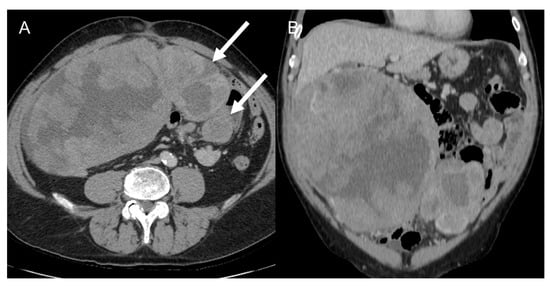

LMS is a smooth muscle tumor [38], more common than LPS in younger age groups [6]. Its most frequent location is the retroperitoneum, near the inferior vena cava [43]. LMS are heterogeneous masses (Figure 4), with irregular peripheral enhancement and enhancing solid portions, mixed with cystic, hemorrhagic, or necrotic areas. LMS show marked T2 hypointensity on MRI and are similar in attenuation to uterine myometrial smooth muscle on CT [39]. Fatty components and calcifications are usually absent [34,38]. The evidence of a large, heterogeneously enhancing, necrotic retroperitoneal mass contiguous with a vessel, with extra- and intraluminal involvement, is highly suggestive of LMS [12,37,43]. It could stem from the inferior vena cava, extending into the intrahepatic portal veins or superior mesenteric vein, or even from small vessels such as renal or gonadic veins. Differentiation from extrinsic compression can be challenging [12,40].

Figure 4.

Retroperitoneal leiomyosarcoma in a 63-year-old woman. Axial (A) and coronal (B) CT images on venous phase show a 10.2 cm heterogeneous mass with central area of low attenuation consistent with necrosis (arrow).